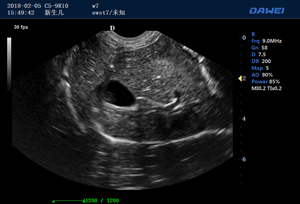

S80高端便攜獸用彩超-彩色多普勒多普勒超聲診斷儀掃描圖 S80高端便攜獸用彩超-彩色多普勒多普勒超聲診斷儀 S80高端便攜獸用彩超-彩色多普勒多普勒超聲診斷儀